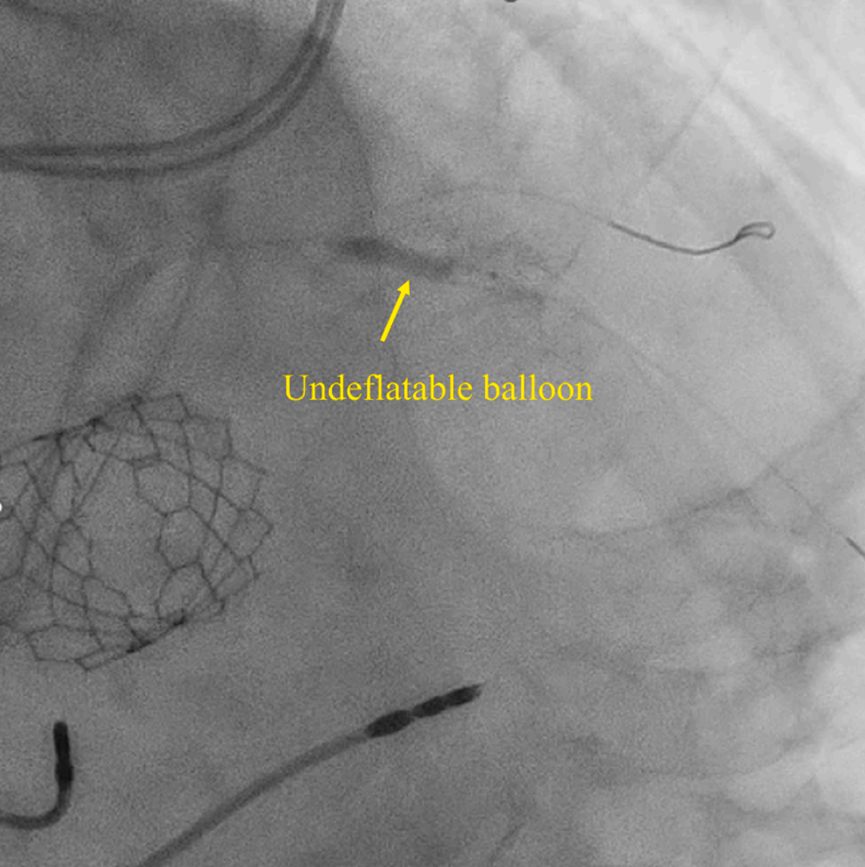

预扩张后植入一枚3.0×33 mm的药物洗脱支架。随后用3.5×15 mm非顺应性球囊以12个大气压对支架进行后扩张,不料球囊扩张后无法排空并卡滞在LAD近端(图1)。为球囊充盈所用的混合液为1:1比例的造影剂与生理盐水。

图1